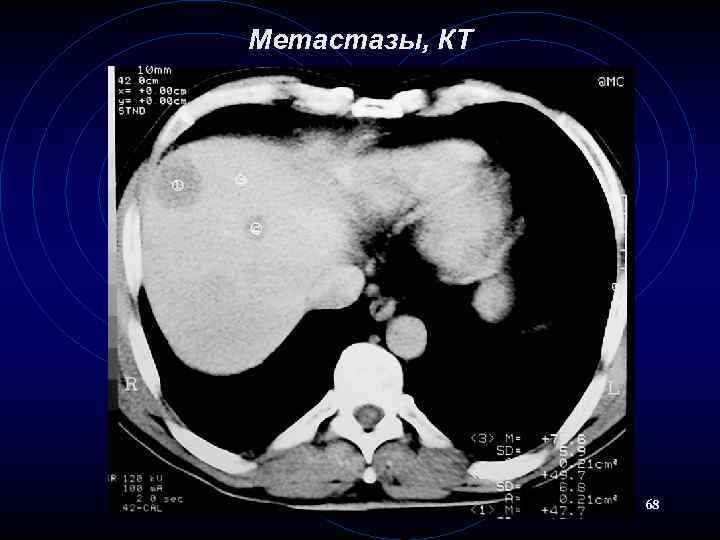

Метастазы, КТ 68